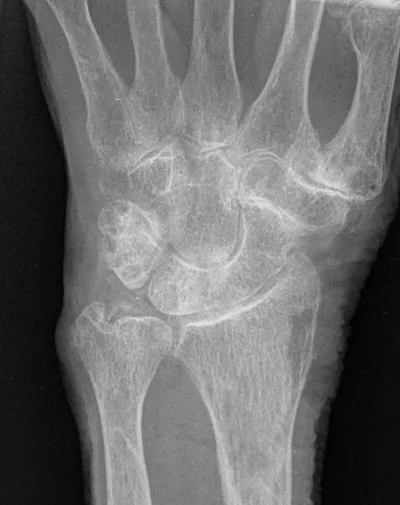

4-Corner carpal fusion of wrist

XRAYHandCarpal+2

4/23/2026